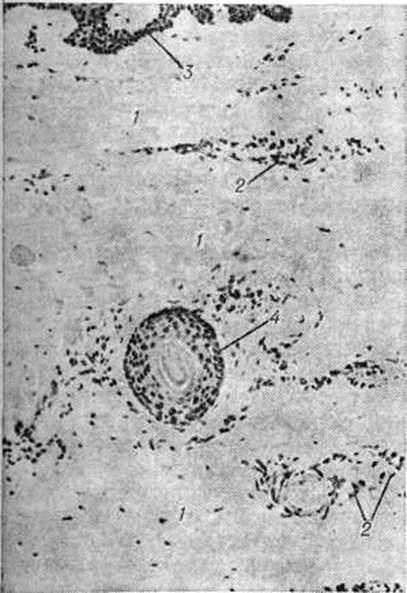

Стадия индурации (рисунок 1) характеризуется склерозом сосочкового и Сетчатого слоёв дермы с запустеванием капилляров, склерозом стенок сосудов, уменьшением количества клеток, утолщением коллагеновых пучков сетчатого слоя и гиалинозом (смотри полный свод знаний), атрофией эпидермиса и придатков кожи, склерозом и гиалинозом подкожной клетчатки. Васкулиты на этой стадии выявляются редко. Клеточные инфильтраты обычно скудные, представлены 3—5 клетками лимфоидного типа.

При активном течении патологический процесса васкулиты артериол и мелких артерий имеют пролиферативный характер с циркулярным разрастанием внутренней оболочки (рисунок 2). При электронной микроскопии в капиллярах поражённых тканей обнаруживается вакуолизация и деструкция эндотелия, а также многослойная базальная мембрана. По данным К луга (Н. Кlug) с соавторами (1977) и другие, при иммунофлюоресцентном исследовании материала, полученного при биопсии почек, мышц и кожи в стенках мелких артерий и капилляров, а также под сарколеммой мышечных волокон обнаружены депозиты IgM и комплемента.